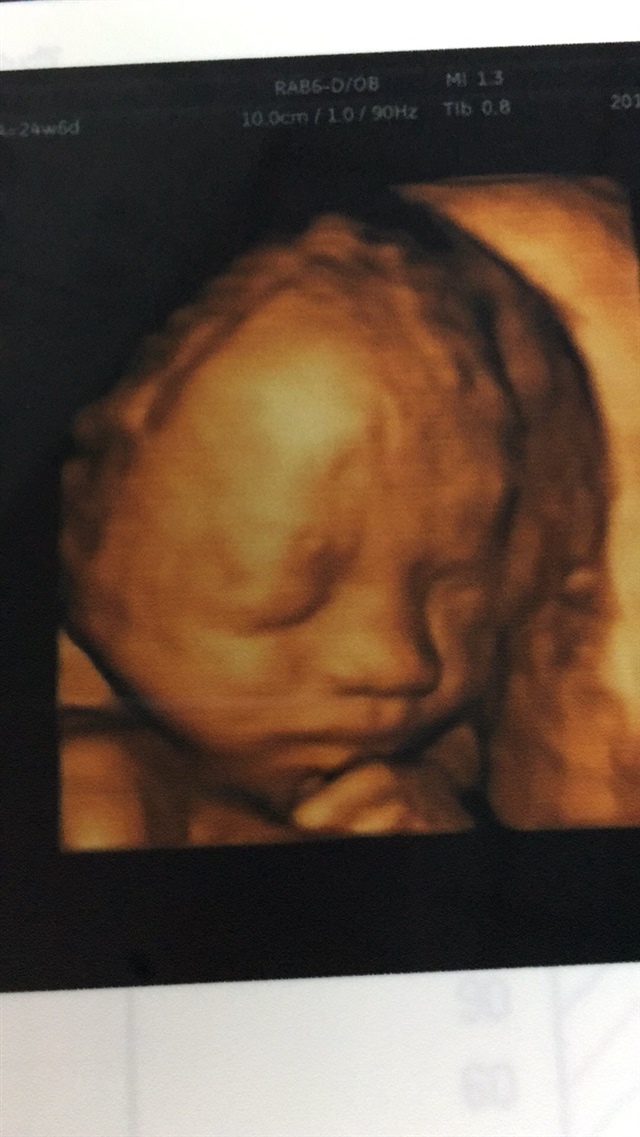

孕27周+5天